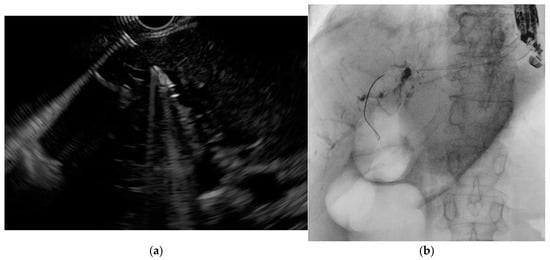

3.2. Pancreatic Duct Cannulation

Selective pancreatic duct cannulation is indicated for various pancreatic disorders, such as idiopathic recurrent acute pancreatitis, chronic pancreatitis, pancreatic ductal injuries, fistula formation, and sphincter of Oddi dysfunction (Figure 5) [22,28]. Pancreatic duct access can be challenging either due to the smaller caliber of the duct or the presence of pathological conditions such as stenosis, stones, or altered anatomy. Typically, smaller-caliber guidewires (0.025- or 0.018-inch) and fully hydrophilic guidewires are used. In very difficult cases, an advanced technique, known as either the reverse double-guidewire cannulation or the bile duct guidewire indwelling method according to different authors, has been described. In this technique, the first guidewire is placed into the biliary duct, which helps keep the papilla open and stabilized, pulls the septum superiorly, and straightens the pancreatic duct, facilitating its cannulation with a second guidewire. This approach can also be useful in cases of parapapillary diverticulum with a deviated papilla and increased papillary mobility, as well as in patients with a tortuous and elongated papillary sphincter muscle [29]. Notably, a case report describes the successful use of an uneven double-lumen cannula (0.025- and 0.035-inch lumens) for the same purpose [30]. Access to the main pancreatic duct (MPD) through the major papilla is sometimes impossible due to pancreas divisum, a distortion of Wirsung’s duct, or other anatomical variations, necessitating minor papilla cannulation [31]. In this setting, experts recommend WGC using small-caliber guidewires (0.018- and 0.021-inch), with or without contrast injection, followed by a standard pull-type sphincterotomy or a needle-knife sphincterotomy over a stent [22]. When the deep cannulation of the dorsal duct with a pull-sphincterotome fails, wire-assisted access sphincterotomy is an alternative technique. After successful deep cannulation with a guidewire, the sphincterotome is exchanged for a needle-knife, which is advanced alongside the wire; then, the minor papilla is incised using the wire as an anatomic guide. Compared to freehand precut sphincterotomy, it ensures early and stable wire access. Additionally, unlike needle-knife sphincterotomy over a stent, it allows for further interventions without requiring stent removal [32].

Figure 5. Guidewire-assisted pancreatic cannulation followed by contrast injection showing a dilated and tortuous main pancreatic duct in the context of chronic pancreatitis.